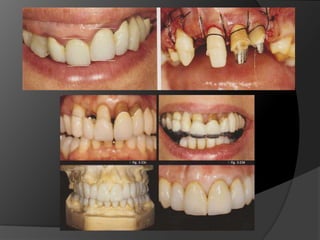

Planificación del TratamientoEl éxito de los tratamientos de rehabilitación está directamente asociado a una planificación correcta y con criterio, que debe ser individualizada y ejecutada con el objeto de atender las necesidades de cada pacientePrótesis Fija. Luiz Fernando Pegoraro

Diagnóstico y Planificación MultidisciplinariaEl examen clínico y la historia clínica nos darán información sobre los factores locales y sistémicos que pueden tener gran influencia en la obtención de un pronóstico para el tratamiento propuesto

Diagnóstico y Planificación MultidisciplinariaHistoria ClínicaAnamnesisFotografía clínica Montaje modelos de estudioEncerados DiagnósticosEvaluación Radiográfica Radiografías PeriapicalesRadiografía PanorámicaEvaluación DentalEvaluación PeriodontalEvaluación EndodónticaEvaluación OclusalEvaluación Articular?